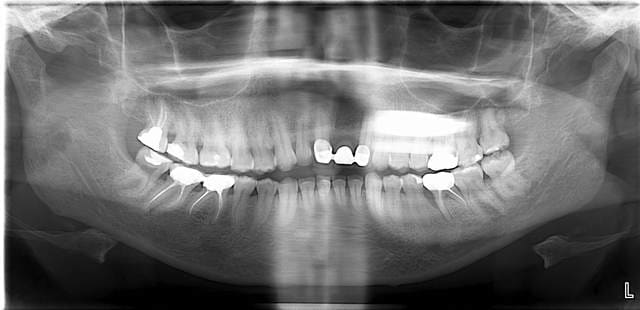

voici la pano

la lésion endo paro sur la 36 sera traitée dans un premier temps, soit par reprise d'endo + curetage paro soit par...extraction!

Merci pour la Pano, les premolaires sup sont en parfait etat, Je maintiens mon option: